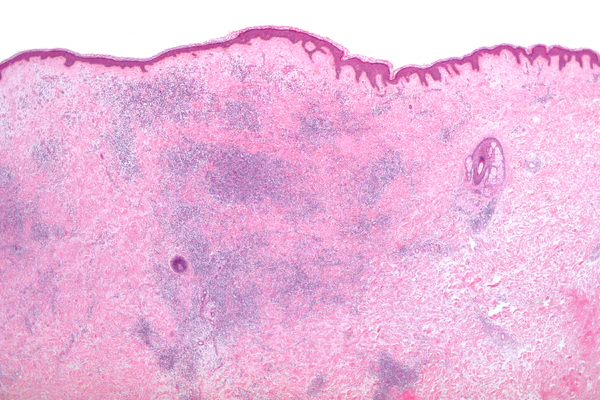

Микроскопия

Гистоморфологические появления укусов насекомых, как правило, характеризуются появлением сосудистого инфильтрата, состоящего из лимфоцитов и эозинофилов.